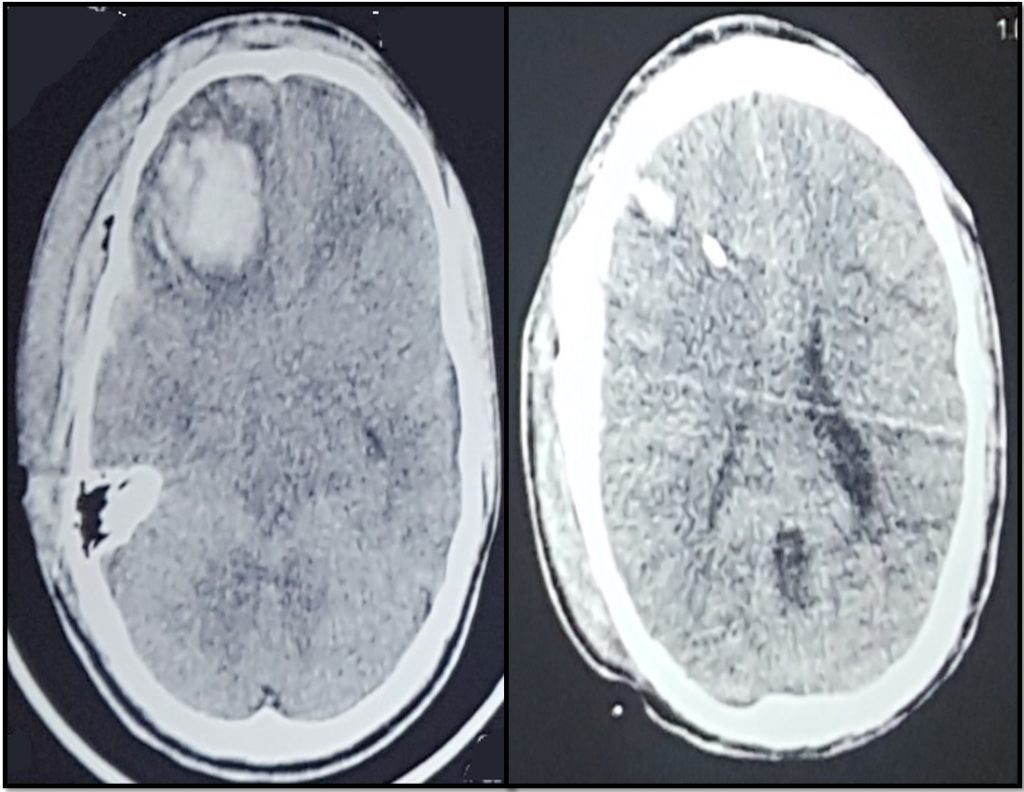

A young 30 years male was presented with road traffic accident with GCS 6/15. Initial CT Scan showed small frontal contusion with basal cisternal obliteration. So ICP cather was placed and patient was managed conservatively in ICU.

Repeat CT showed enlargement of frontal contusion. ICP was approaching to 37 and ICP A is 14 that is reflected the abnormal waveform.

Post op ct scan showing adequate decompression.